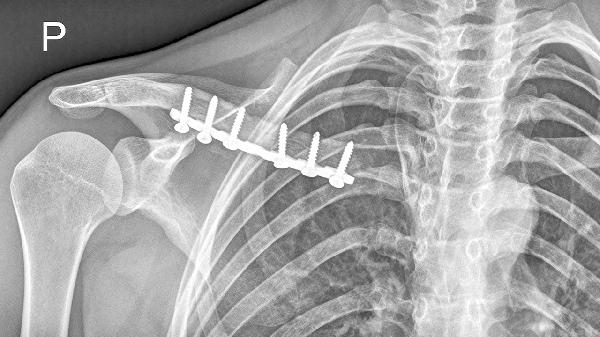

鎖骨骨折吃啥能恢復(fù)的快些

鎖骨骨折后可通過高蛋白飲食、鈣質(zhì)補(bǔ)充、維生素D攝入、抗氧化食物及適量膠原蛋白促進(jìn)恢復(fù)?;謴?fù)速度主要與營養(yǎng)攝入、骨折類型、年齡、康復(fù)訓(xùn)練及并發(fā)癥控制等因素相關(guān)。

鎖骨骨折恢復(fù)期需建立科學(xué)的飲食計(jì)劃,每日保證3-4餐均衡營養(yǎng)。急性期過后可逐步增加低強(qiáng)度上肢活動,如握力訓(xùn)練、鐘擺運(yùn)動等促進(jìn)血液循環(huán)。避免吸煙飲酒影響骨愈合,控制咖啡因攝入減少鈣流失。睡眠時保持30-45度半臥位減輕疼痛,定期復(fù)查X線觀察骨痂形成情況。若出現(xiàn)異常腫脹、持續(xù)疼痛或皮膚感覺異常需及時就醫(yī)。